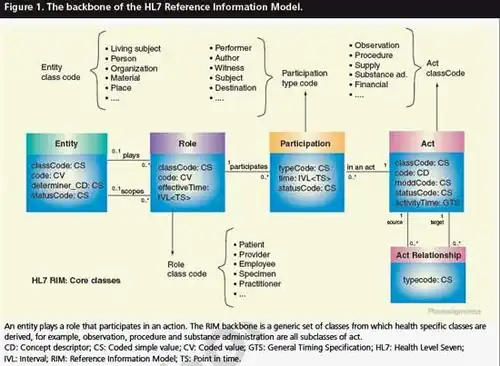

Health level 7 (HL7) standards